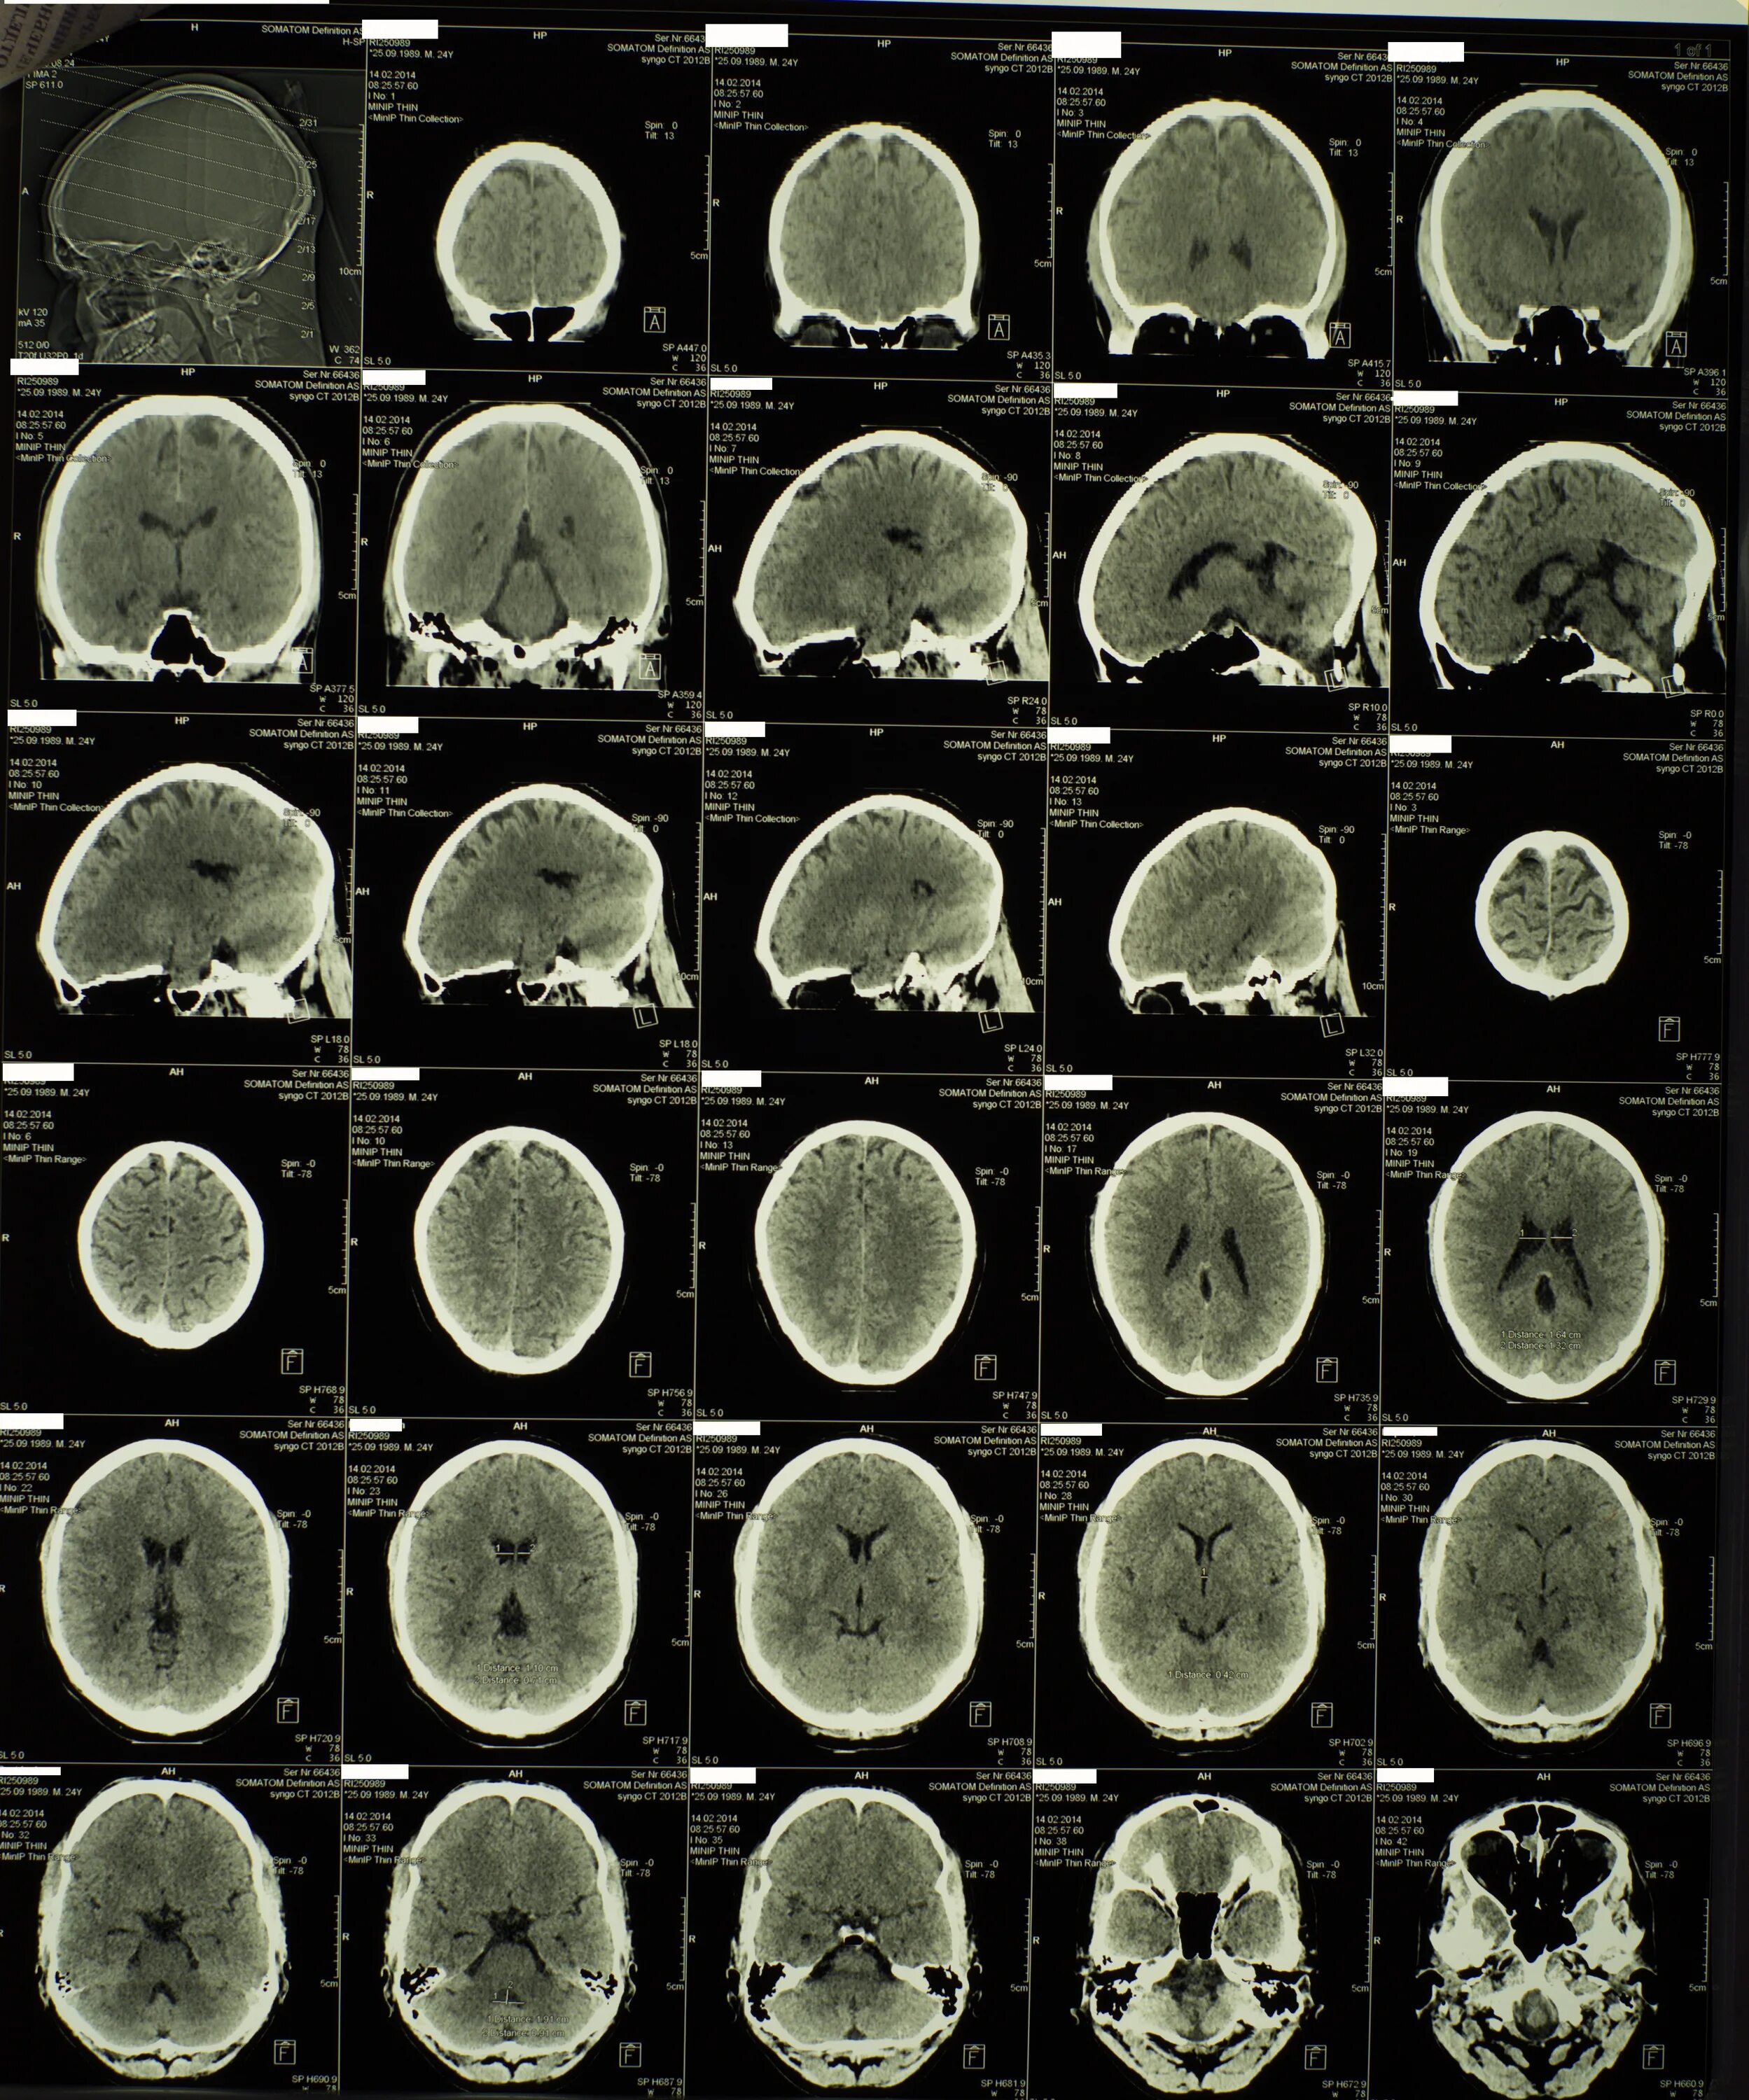

Кт пример